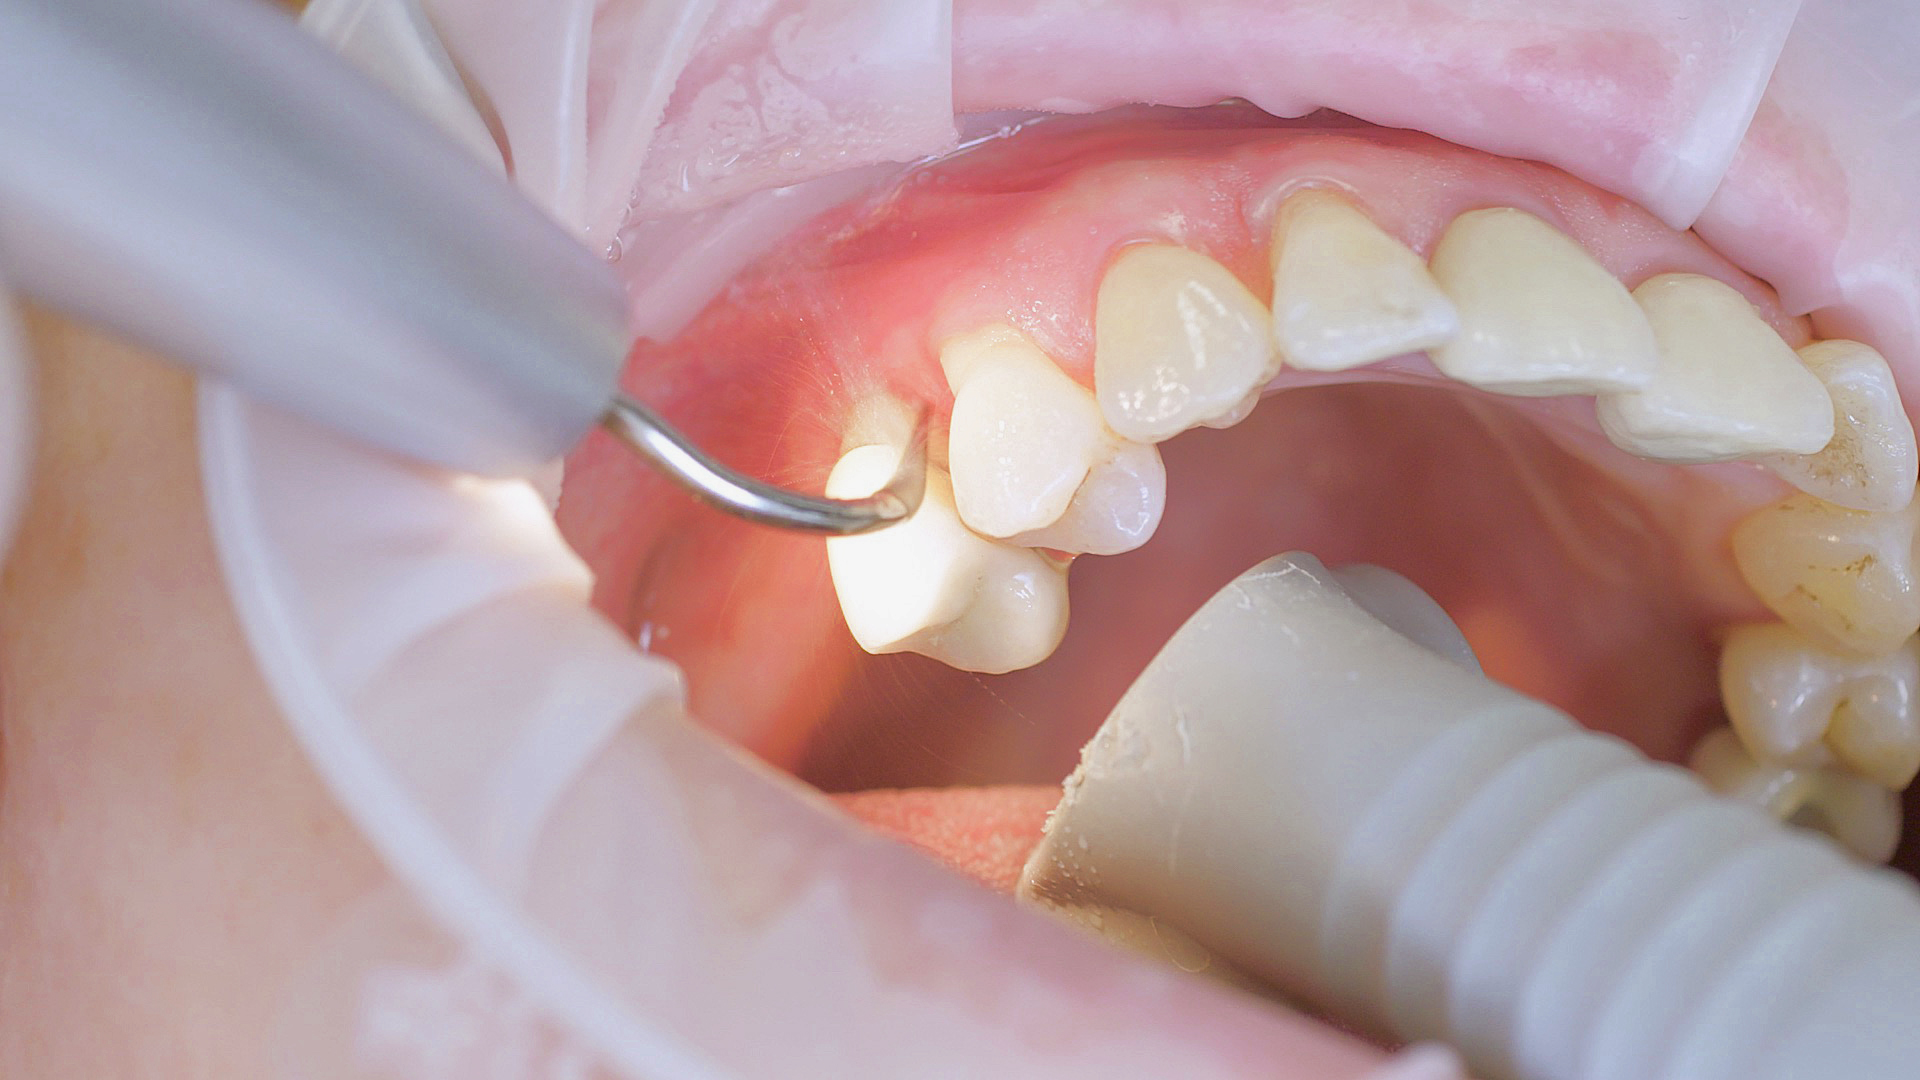

Every dental examination is based on a detailed medical history combined with targeted diagnostics con- taining as much detail as possible: The dentist records systemic risk factors such as diabetes or smoking and identifies any potential increased tendency to inflammation.[3] Hard and soft tissues are examined and periodontal pockets are probed in a screening test according to PSR (Periodontal Screening and Recording). In case of abnormal findings, the periodontal status is then re- corded and therapy is initiated where necessary. This treatment begins with professional biofilm management, by using, for example, rotary cups and polishing com pounds (Fig. 1), and comprehensive instructions in oral hygiene. Sonic or ultrasonic systems remain an effective alternative or supplement to manual instruments for sub- gingival debridement and biofilm management (presentation by Prof. Dr Ulrich Schlagenhauf;

Fig. 2). Supplementary use of photodynamic therapy, air polishing or local and systemic antibiotics is not adequately documented (Prof. Dr Sema Hakki).[4] According to Dr Sergio Bizzarro, improved biomarker diagnostics may lead to an increase in customised patient therapy in the future.